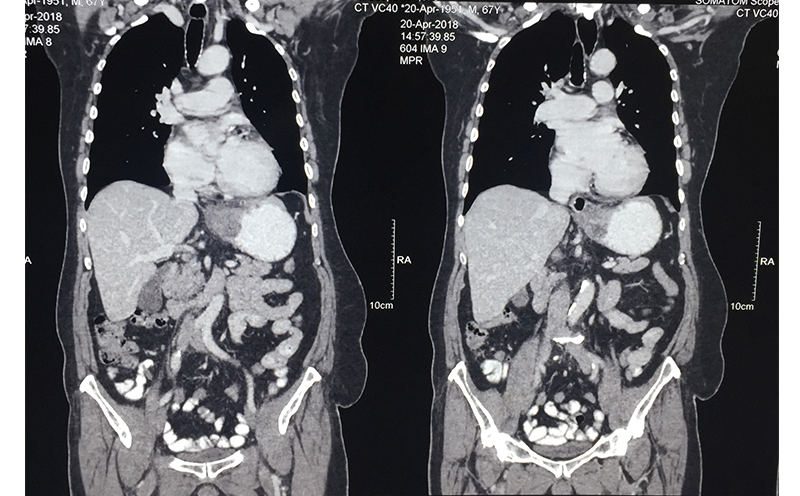

63 year old male patient was diagnosed with cancer of upper part of stomach. Patient was fit for a curative surgery on investigations. However a staging laparoscopy (endoscopy of the abdominal cavity – a type of surgery prior to main surgery) revealed a solitary deep seated lymph node spread even missed by PET-CT scan. An intraoperative frozen section histopathology (rapid test) confirmed the cancer in the lymph node. A chemoport (special system for delivering chemotherapy to avoid the trouble of searching patent veins) was inserted during the same surgery. Chemoport insertion is a surgery done regularly for patients in need of chemotherapy. Patient received 8 cycles of chemotherapy and then underwent a repeat PET-CT scan to confirm absence of metastasis. Complete stomach (including cancer bearing part) along with draining lymph nodes (lymphadenectomy) was removed successfully 4 weeks after the last cycle. A gap of 4-6 weeks is mandatory between chemotherapy cycle and major surgery to reduce risk of postoperative complications. He was put back on chemotherapy 6 weeks after the surgery and received 6 more cycles. Patient is fit and alive for 1 & ½ years since surgery.

When a stomach cancer is suspected in any patient, he/she is subjected to an endoscopy of the stomach (internal visualization). This helps in diagnosis and taking a biopsy for confirmation. A CT scan is performed after the confirmation (though often patients come with a CT scan diagnosis) to see whether the cancer can be removed surgically. A PET-CT is performed prior to any therapy to see the spread / extent / stage of the disease. If the tumor is in early stage, stomach (part / full depending on which part of stomach is involved and extent) along with the tumor and surrounding lymph nodes is removed and small intestine is joined with the proximal stomach or esophagus. If the tumor is small and lymph node spread is less, this operation is done laparoscopically. A chemoport may also be placed at this time for postoperative chemotherapy (adjuvant) unless it is a very early stage disease. Very early stage cancer can sometimes be removed through an endoscopic procedure (endoscopic mucosal resection --EMR / endoscopic submucosal dissection – ESD) under the guidance of an endoscopic ultrasound equipment. Unfortunately this is very rarely possible in Indian patients since disease is advanced by the time it is diagnosed.

If the disease is diagnosed at a stage where it is advanced in the stomach walls and surrounding region with large lymph nodes then a preoperative (neoadjuvant) chemotherapy is given to downstage the disease. If this attempt is successful and tumor responds, then in that case a curative surgery is done. This is followed by further chemotherapy cycles. Occasionally external radiotherapy is given too. This kind of multidisciplinary treatment plan was used in the above case.